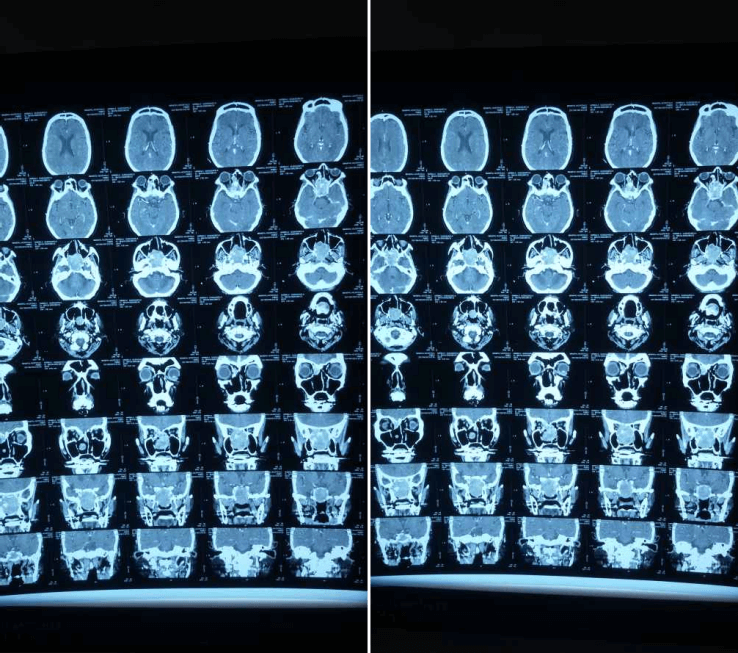

2012 সালের অক্টোবরে তিনি আমাদের কাছে ফিরে এসেছিলেন, ধীরে ধীরে প্রগতিশীল ডান-পার্শ্বযুক্ত নাক ব্লক, ফুসফুস অনুনাসিক স্রাব এবং মাঝে মাঝে 2-বছরের মাথাব্যথার অভিযোগ করেছিলেন। এপিস্ট্যাক্সিস বা অন্যান্য ইএনটি অভিযোগের কোন ইতিহাস ছিল না। পরীক্ষায়, নাকের ডান দিকে মসৃণ পৃষ্ঠ ভরাট করে একটি বড় ভর ছিল, স্পর্শে রক্তপাত হয়নি। এবং একটি স্থূল DNS বাম. মস্তিষ্কের এমআরআইতে দেখা গেছে যে একটি মিশ্র তীব্র ক্ষত মাথার খুলির স্ফেনয়েড, ইথময়েড সাইনাস এবং সেলা এবং ক্লিভাসের অংশে অনুপ্রবেশ করে। সমস্ত রুটিন রক্ত এবং প্রস্রাব তদন্ত স্বাভাবিক ছিল. ক্ষতের বায়োপসি ইনভার্টেড প্যাপিলোমার পুনরাবৃত্তির পরামর্শ দিয়েছে। তিনি টিউমারের এন্ডোস্কোপিক ডিবুলিং করান। HPE এই সময় hemangiopericytoma পরামর্শ ছিল.